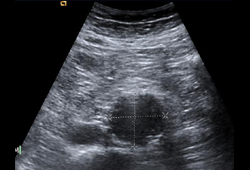

- masa abdominal pulsátil palpable